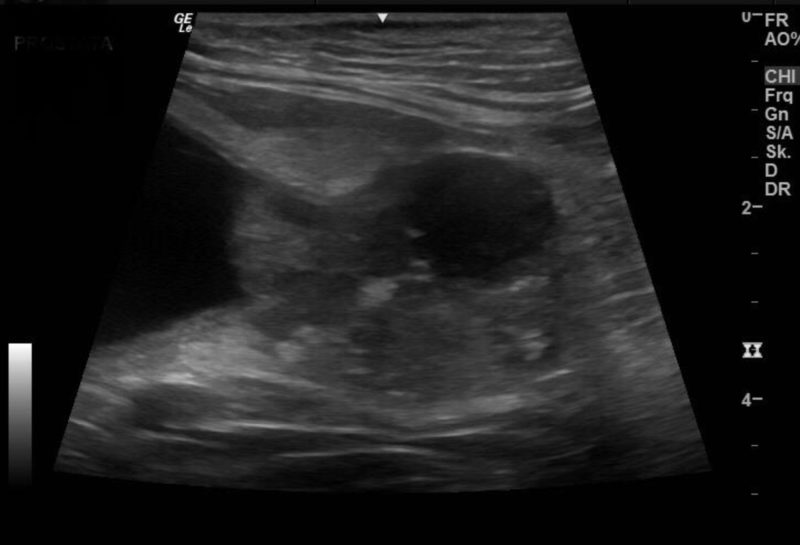

Ein anderer Fall ist der eines neun Jahre alten Kooikerrüden, der bereits mit Antibiotika anbehandelt war und wenig bis keinen Urin absetzen konnte. Der Rüde war seit zwei Jahren kastriert. Röntgenologisch zeigten sich eine stark gefüllte Harnblase und eine röntgendichte prominente Vorsteherdrüse (Prostata). Sonographisch stellte sich diese inhomogen, mit einer teilweisen Ansammlung von Calciumsalzen (kalzifiziert) dar. Im Bereich der Prostata schien eine blumenkohlartige Wucherung in der Harnröhre vorzuliegen, die den Urinabsatz blockierte.

Verdachtsdiagnose: Karzinom

Es wurden eine Urinprobe und per Ansaugbiopsie eine Probe der Veränderung in der Harnröhre entnommen und ein Blasenkatheter zur Entlastung der Harnblase angelegt. Bereits in der mikroskopischen Untersuchung vor Ort wurde die Verdachtsdiagnose eines Karzinoms gestellt. Bei dem Hund wurde eine Blasenspiegelung (Zystokopie) durchgeführt, in der weitere Proben zur pathohistologischen Untersuchung entnommen und eine Erweiterung der prostatischen Harnröhre mittels Laserablation durchgeführt wurden. Die pathohistologische Untersuchung ergab das Ergebnis eines Übergangszellkarzinoms. Das Übergangszellkarzinom (ÜZK) ist bösartig und sehr aggressiv - daher ist eine schnellstmögliche Behandlung entscheidend für eine positive Prognose des betroffenen Vierbeiners.